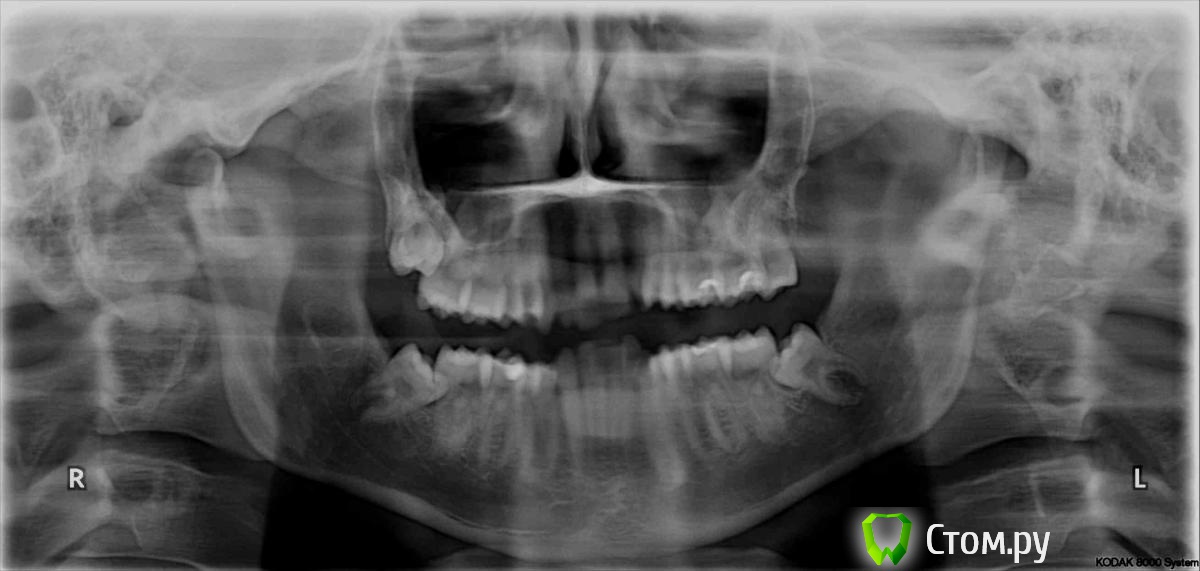

Татьяна_200 Опубликовано 20 августа, 2014 Поделиться Опубликовано 20 августа, 2014 Подскажите пожалуйста, есть ли необходимость удалять верхние восьмерки? Вроде скученности вверху особой нет. Удаление восьмерок непростое всегда, рядом пазухи , стоит ли ? Ссылка на комментарий

Korel Опубликовано 25 августа, 2014 Поделиться Опубликовано 25 августа, 2014 Вам надо убирать ВСЕ 4 восьмёрки. Начните с нижних. Ссылка на комментарий